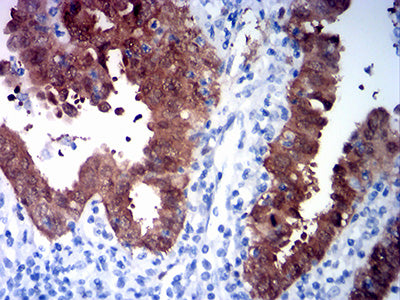

Immunohistochemical analysis of paraffin-embedded human ovarian cancer tissues using CDKN2A mouse mAb with DAB staining.

Immunohistochemical analysis of paraffin-embedded human endometrial cancer tissues using CDKN2A mouse mAb with DAB staining.